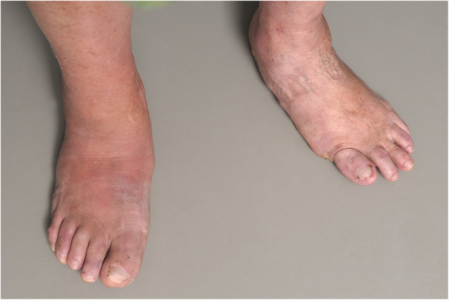

处于急性活动期的Charcot足:右脚红肿